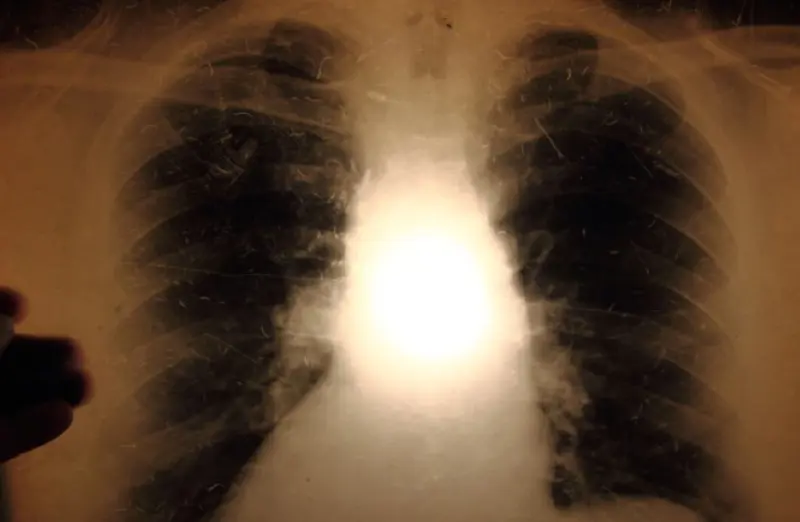

Tuberculosis is caused by the mycobacterium tuberculosis. The disease usually occurs in the lungs (pulmonary tuberculosis), but can affect all the organs in the body.